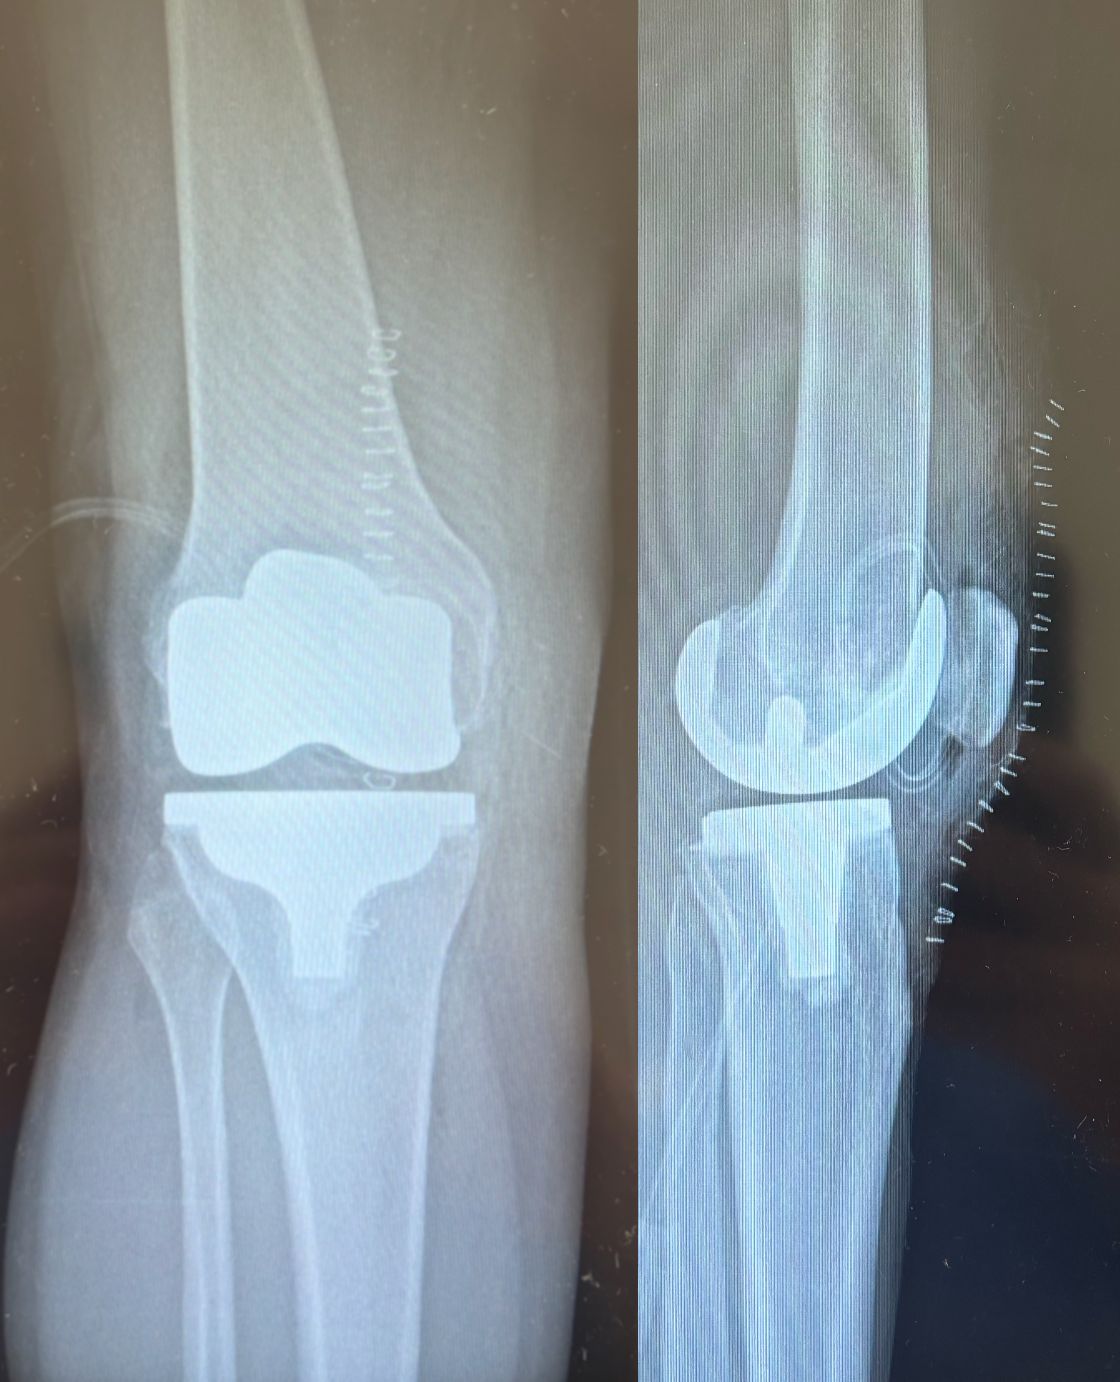

Ho maturato una solida esperienza nella chirurgia protesica mini-invasiva di anca e ginocchio. Eseguo interventi di protesi di anca mediante accesso anteriore “bikini” e accesso posterolaterale, interventi di protesi di ginocchio sia monocompartimentale che totale. Tratto la traumatologia sportiva di ginocchio e spalla mediante l’utilizzo di tecniche artroscopiche mini-invasive.